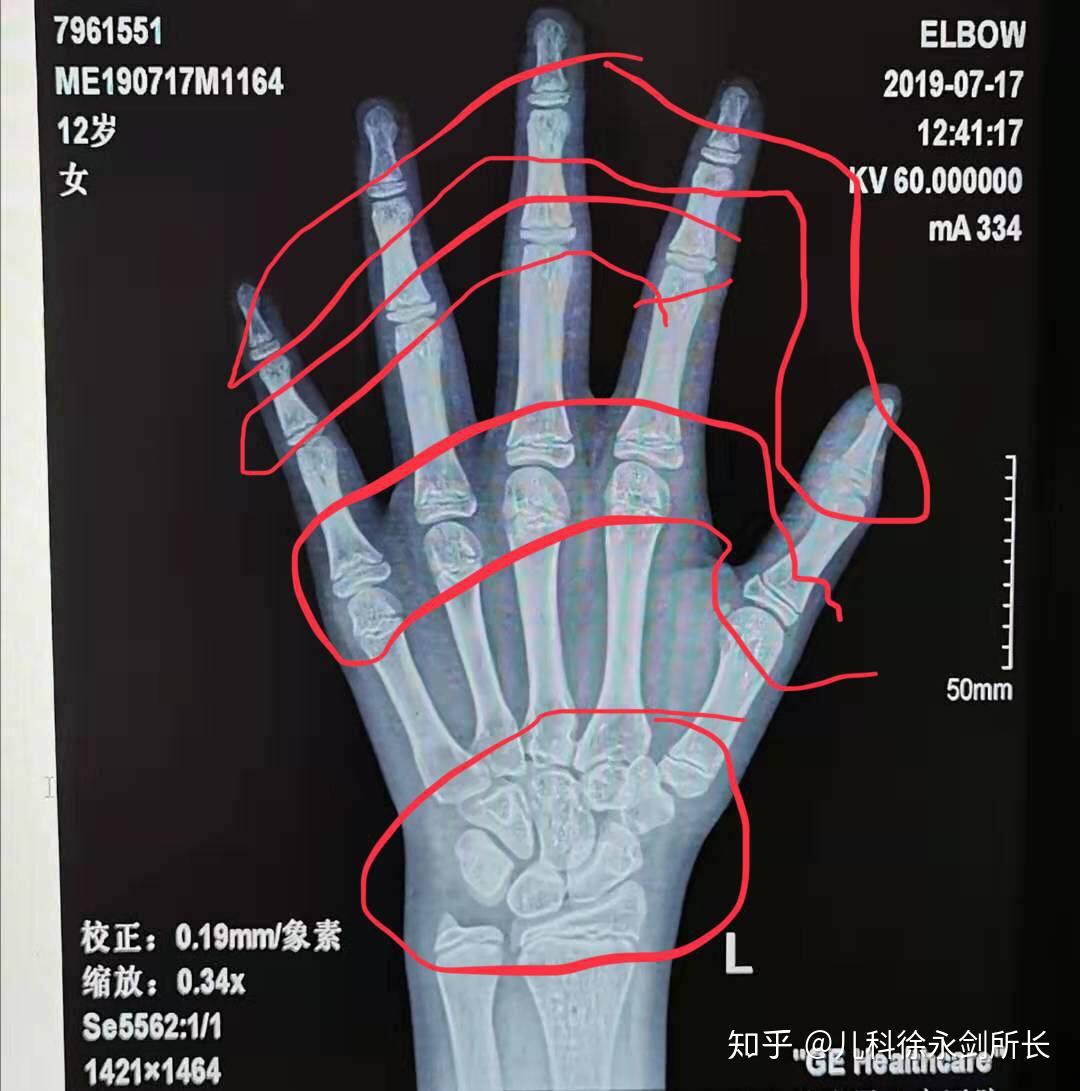

帮忙看看这个骨龄片,12周岁六个月的男孩子,骨龄片上显示骨龄多少岁?

图片尺寸768x1024